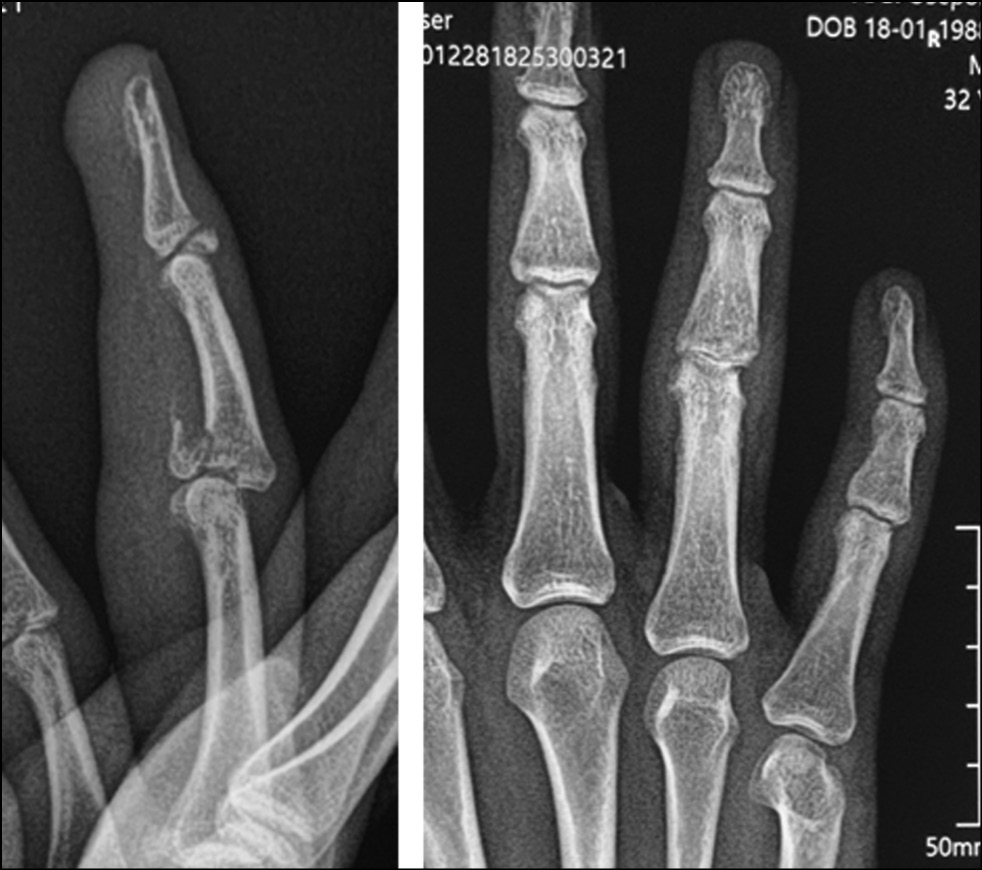

Fig. 2. X-ray picture.

Fig. 25. X-ray picture before surgery.

Fig. 26. X-ray control after surgery. Suzuki pins and rubber traction system.

All patients underwent preoperative diagnostics: radiography, computed tomographic study, and clinical evaluation of the range of motion in the joint. According to the radiological and tomographic signs, the fractures of the palmar edge of the base of the middle phalanx with its dorsal subluxation, and in three cases fractures of the dorsal edge of the base of the middle phalanx with palmar subluxation, accompanied by failure of the central bundle of the tendon of the common extensor tendon of the finger, were determined as malunion fractures. According to the Eaton classification, they are categorized as groups IIIa and IIIb. In all cases, the amplitude of movements in PIP joints was sharply limited; flexion was up to 30°. Pain syndrome at the moment of attempted flexion in the joint was assessed by patients ranging from three to four points on VAS.